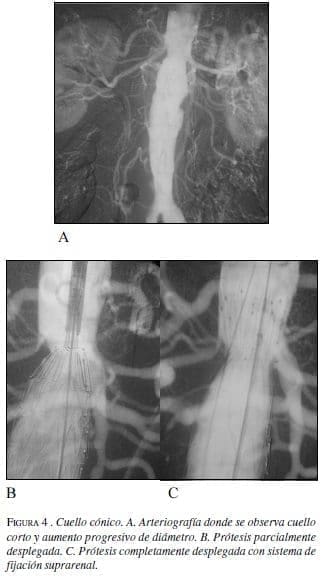

• Cónicos:

Cuando el cuello se ensancha en sentido distal constituye una contraindicación relativa para el tratamiento endovascular, se considera que la conicidad impide una buena aposición entre la endoprótesis y la pared del vaso, pudiendo predisponer a migraciones y a la presencia de fugas tipo 1.

Se considera presente la conicidad en caso de un incremento mayor del 10% en el diámetro del vaso en una longitud de 15 mm en el cuello aórtico proximal.

Los cuellos cónicos tienen difícil tratamiento, y en caso de tratarse, se debe elegir una prótesis que permita una fijación suprarrenal y posteriormente elegir el diámetro de acuerdo con el diámetro más distal al origen de las arterias renales, entre 15 y 20 mm de longitud, recomendados como diámetro de elección de la prótesis, haciendo que ésta se vaya aplicando a la pared conforme se acerca al aneurisma (figura 4).